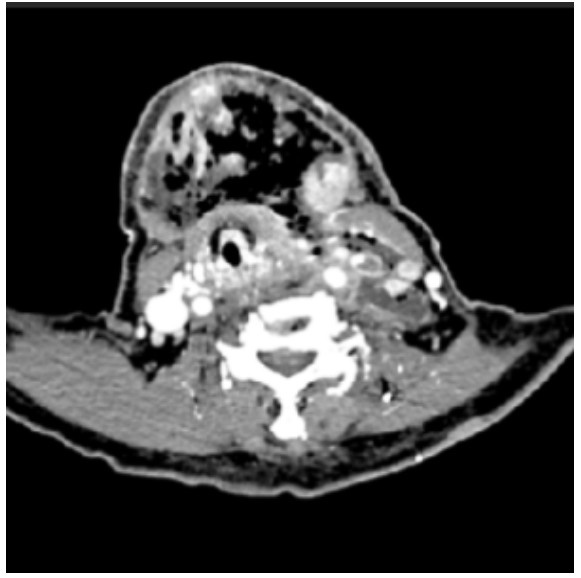

1 病历资料 1.1 一般资料患者女,78岁,因“左脸颊肿胀伴咽痛6 d,发热1 d”送本院急诊就诊。主诉8 d前有化粪池接触史,6 d前出现咽痛,当地医院予抗生素、激素治疗后病情进一步加重。查体:体温38.6 ℃,血压79/43 mmHg,呼吸22次/min,心率104次/min,血糖14.8 mmol/L,左侧颜面部及下颌发红肿胀,皮温升高,张口受限。实验室检查:白细胞计数13.4×109/L,血小板计数5×109/L(危急值),C反应蛋白108.7 mg/L,降钙素原11.75 ng/mL,D-二聚体2 090 µg/L。头颈部CT检查(图 1)示:鼻咽、口咽部、下颌部软组织炎性病变首先考虑,两侧颈部多发肿大淋巴结,鼻咽左侧壁局部稍增厚,同侧咽隐窝及咽鼓管开口闭塞。初步诊断:(左侧)咽旁间隙感染、(左侧)颌下感染、颈部软组织感染(脓肿形成)、血小板减少、脓毒性休克。

| 图 1 头颈部增强CT(轴位) |